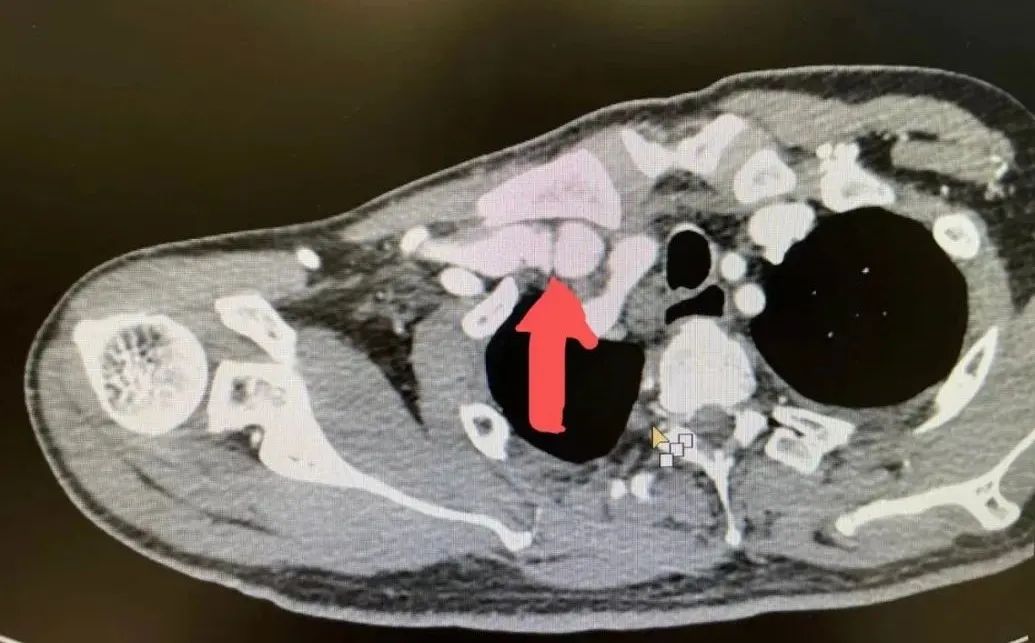

肾内科张东亮主任医师在透析室查房中听了患者的叙述,给出了诊断“静脉高压综合征”,随后立刻为金大叔安排检查。首先是超声明确内瘘吻合口内径及血内瘘流量,未见明显异常。随后又进行了上肢及深静脉CT三维重建(CTA+CTV),发现主要病变为锁骨下静脉瓣增生狭窄(图1)。

图1